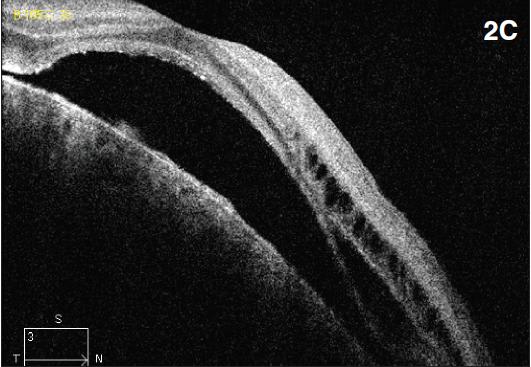

Figure 2. Diffuse choroidal hemangioma. The patient was a nine-year-old boy with history of Sturge-Weber syndrome, referred due to decreased vision (20/200) and subretinal fluid in the right eye. The fundus exam revealed retinal pigment epithelium mottling around the optic nerve with a surrounding cuff of subretinal fluid (A). B-scan ultrasonography demonstrated a solid, highly echogenic lesion, with diffuse choroidal thickening (B). OCT showed subretinal fluid with cystic spaces in the outer retinal layers (C). One year after treatment with external beam radiotherapy (20 Gy in 10 fractions, 2 Gy/fraction), the fundus exam revealed a regressed hemangioma (D). Tumor regression was confirmed by B-scan ultrasonography (E). Concomitant resolution of subretinal fluid was noted on OCT (F). Visual acuity improved to 20/60.

B-scan ultrasonography demonstrates solid, highly echogenic lesions, with diffuse choroidal thickening (Figure 2b), and high internal reflectivity on A-scan. Early hyperfluorescence with persistence of hyperfluorescence through the late phases of the angiogram are seen with fluorescein angiography. Similar findings are observed on ICG, with a characteristic lacy intrinsic vascular pattern, with a diffuse distribution.16 OCT may be used to confirm the presence of subretinal fluid (Figure 2c).